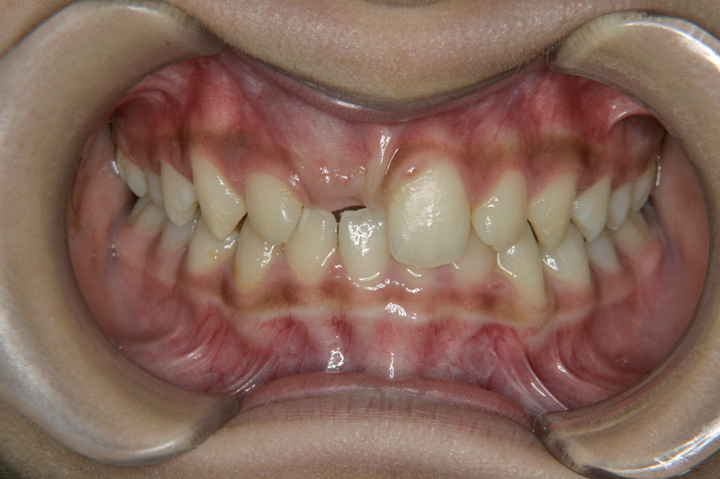

過蓋咬合(深いかみ合わせ)

埋伏歯

右上1番目の歯が生えてこないことを気にされて来院された10歳の女子です。非抜歯でデーモンシステムを用いて歯の配列を行い、良好な結果を得ることができました。ボンデッドワイヤーとエシックスを併用した保定に移行しております。

初診時